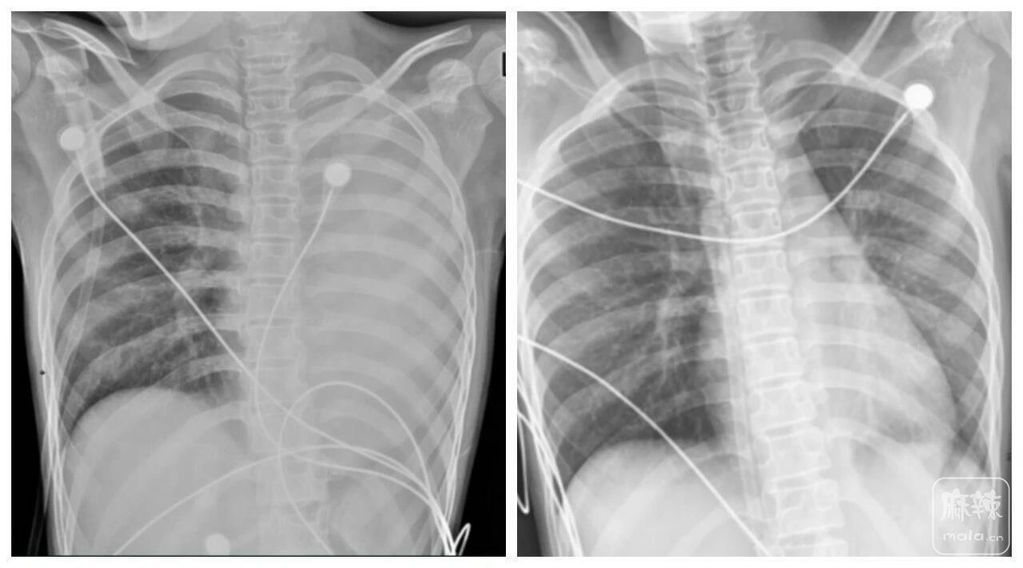

一开始,她只是轻微咳嗽,发热后在外院检查提示肺炎、肺不张,转诊到浙大四院儿科时,笑笑出现呼吸急促、胸闷胸痛,血氧饱和度勉强维持在90%左右,胸片显示左肺已完全呈“白肺”改变,病情急剧恶化。

△笑笑治疗前,左肺呈“白肺”状态,治疗后“白肺”被吸收,心脏边缘清晰可见。图源:浙大四院